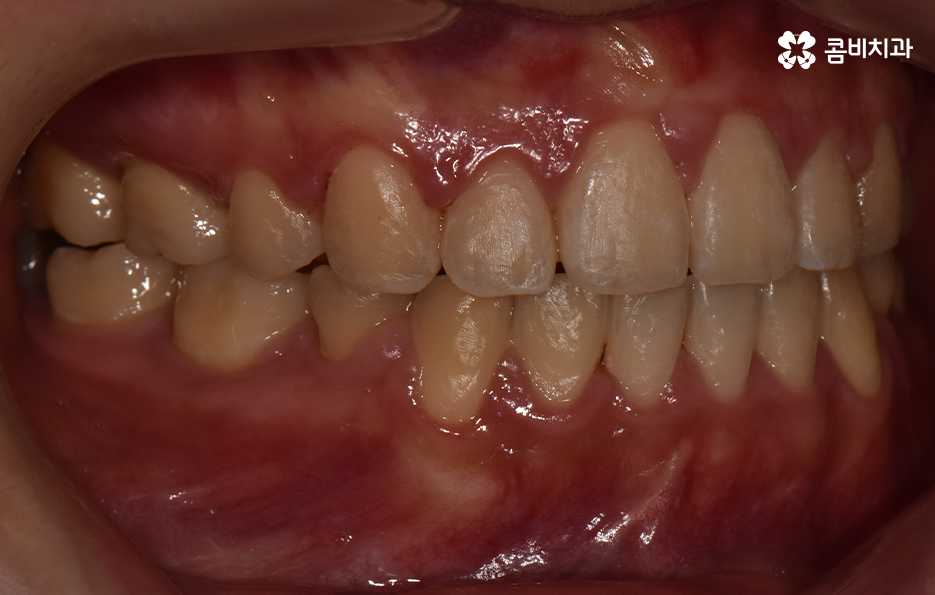

돌출입을 개선하기 위한 교정 치료의 사례에도 돌출입발치교정 사례가 많은 이유도 치아의 발치를 통해 앞니를 후방 이동시키는 치아 교정의 원리가 있기 때문이라고 설명할 수 있어요

이처럼 치열의 변화는 얼굴형 변화에도 많은 영향을 줄 수 있기 때문에 치아교정의 만족도는 치열뿐 아니라 환자 개개인의 골격과 얼굴형을 고려하여 잘 어울리는 조화적인 측면과 치아의 건강 등 고려해야 할 점이 많다는 것을 알 수 있는데요

오늘은 돌출입발치교정 통해서 치열도 가지런하게 교정하고 얼굴형의 변화뿐 아니라 교합까지 잘 맞물려서 건강하게 치아교정을 하는 방법에 대해 알아볼 거예요

보편적으로 돌출입발치교정 통해 치료가 진행되면 돌출입이 개선되는 경우가 대부분이지만 앞니의 각도나 턱뼈와의 상관관계 등을 고려할 때 치아교정 만으로는 치료의 만족도가 높지 않은 경우도 있는데요. 이 경우 외과 수술이 동반되어야 할 수 있습니다.

치아교정을 잘하기 위해서는 자신의 구강 구조 및 얼굴형 등을 종합적으로 정밀 검진하여 경험 많은 교정 전문의와 충분한 상담의 필요하며 수많은 돌출입발치교정 사례가 존재하기에 나에게 맞는 치료 방법을 잘 아는 것이 중요하다는 것을 강조드리고 있어요